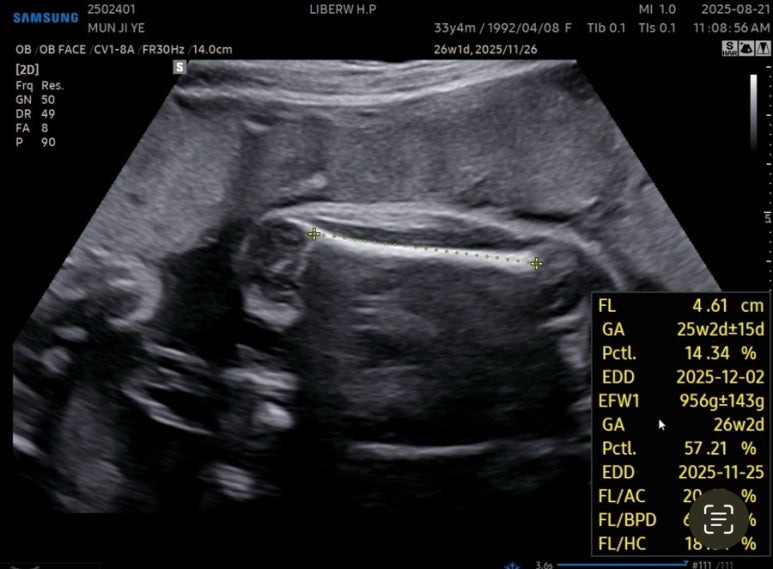

27주차 사탕이는

머리둘레 6.62cm

배 둘레 22.91cm

다리길이 4.61cm

몸무게 956g

심장박동수 150bpm

경부길이 3.44cm

양수량도 적당했다